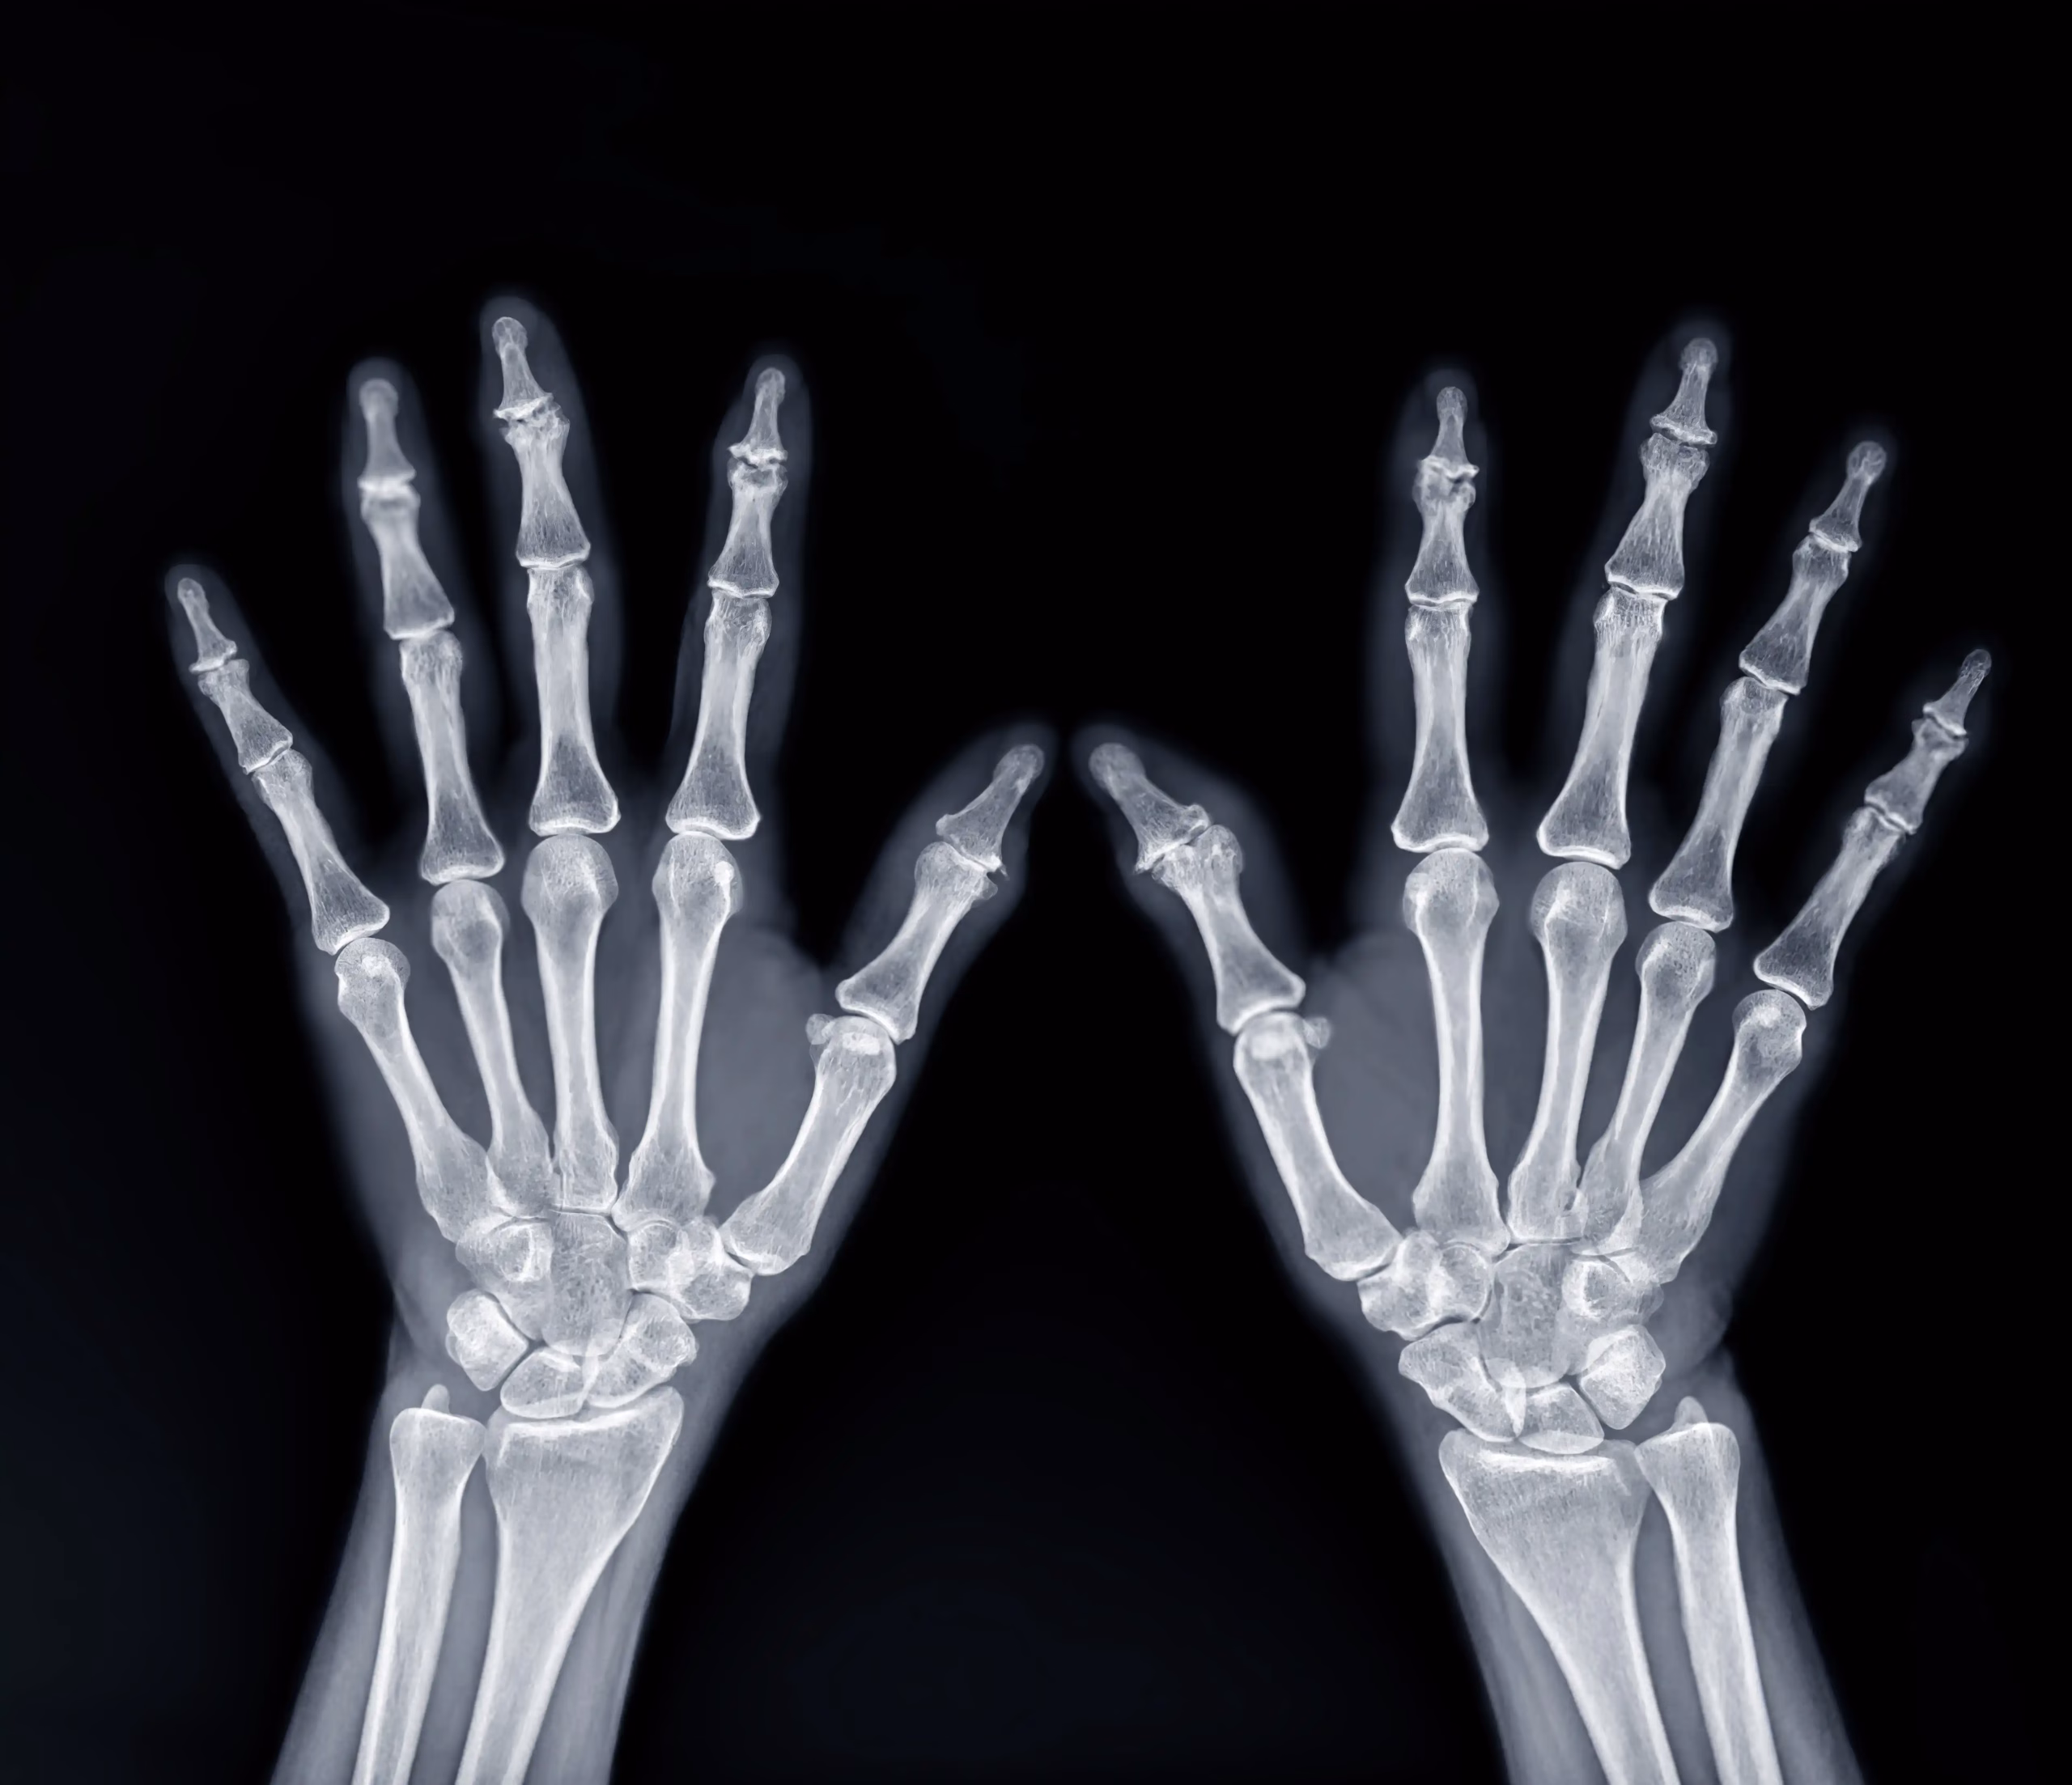

🮽 Pumn, mână și degete

• Artroză interfalangiană, rizoartroză

• Fracturi scafoid, metacarpiene, falange

• Eroziuni în poliartrită reumatoidă